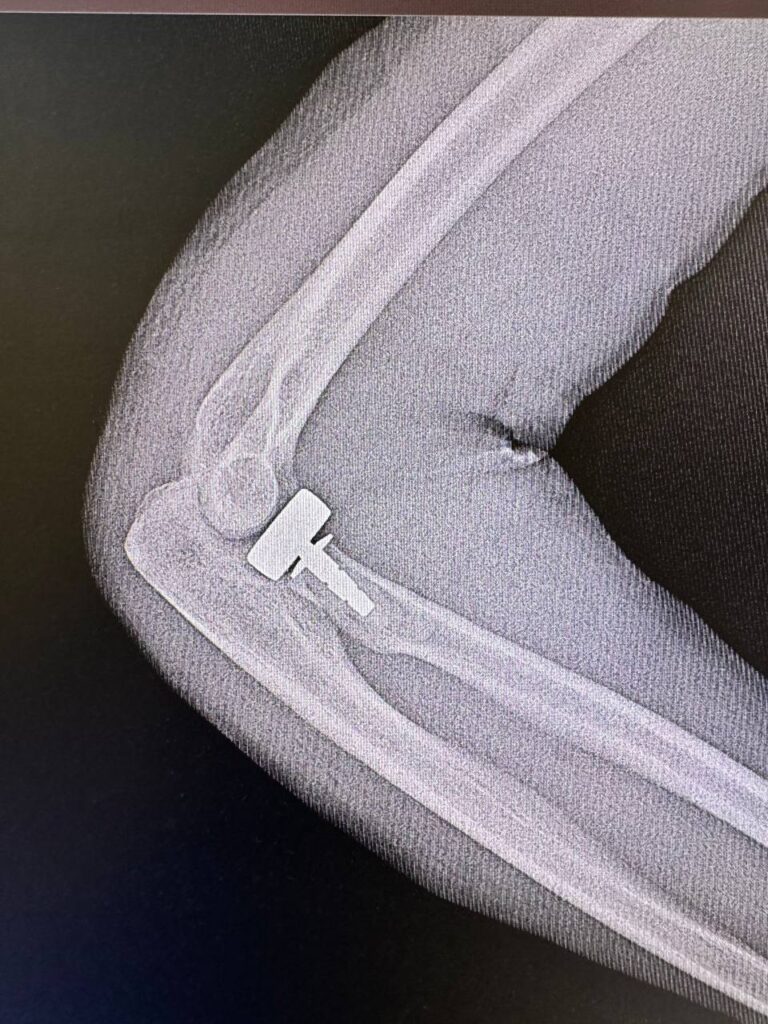

В своем ТГ-канале 2 августа губернатор Оренбуржья Денис Паслер рассказал о новом достижении наших хирургов. Специалисты оренбургского центра хирургии и травматологии выполнили уникальную операцию по протезированию головки лучевой кости.

В анамнезе у 23-летнего пациента был оскольчатый перелом. Чтобы восстановить функцию локтевого сустава и потребовалась эта операция. Теперь молодой человек сможет нормально работать рукой.